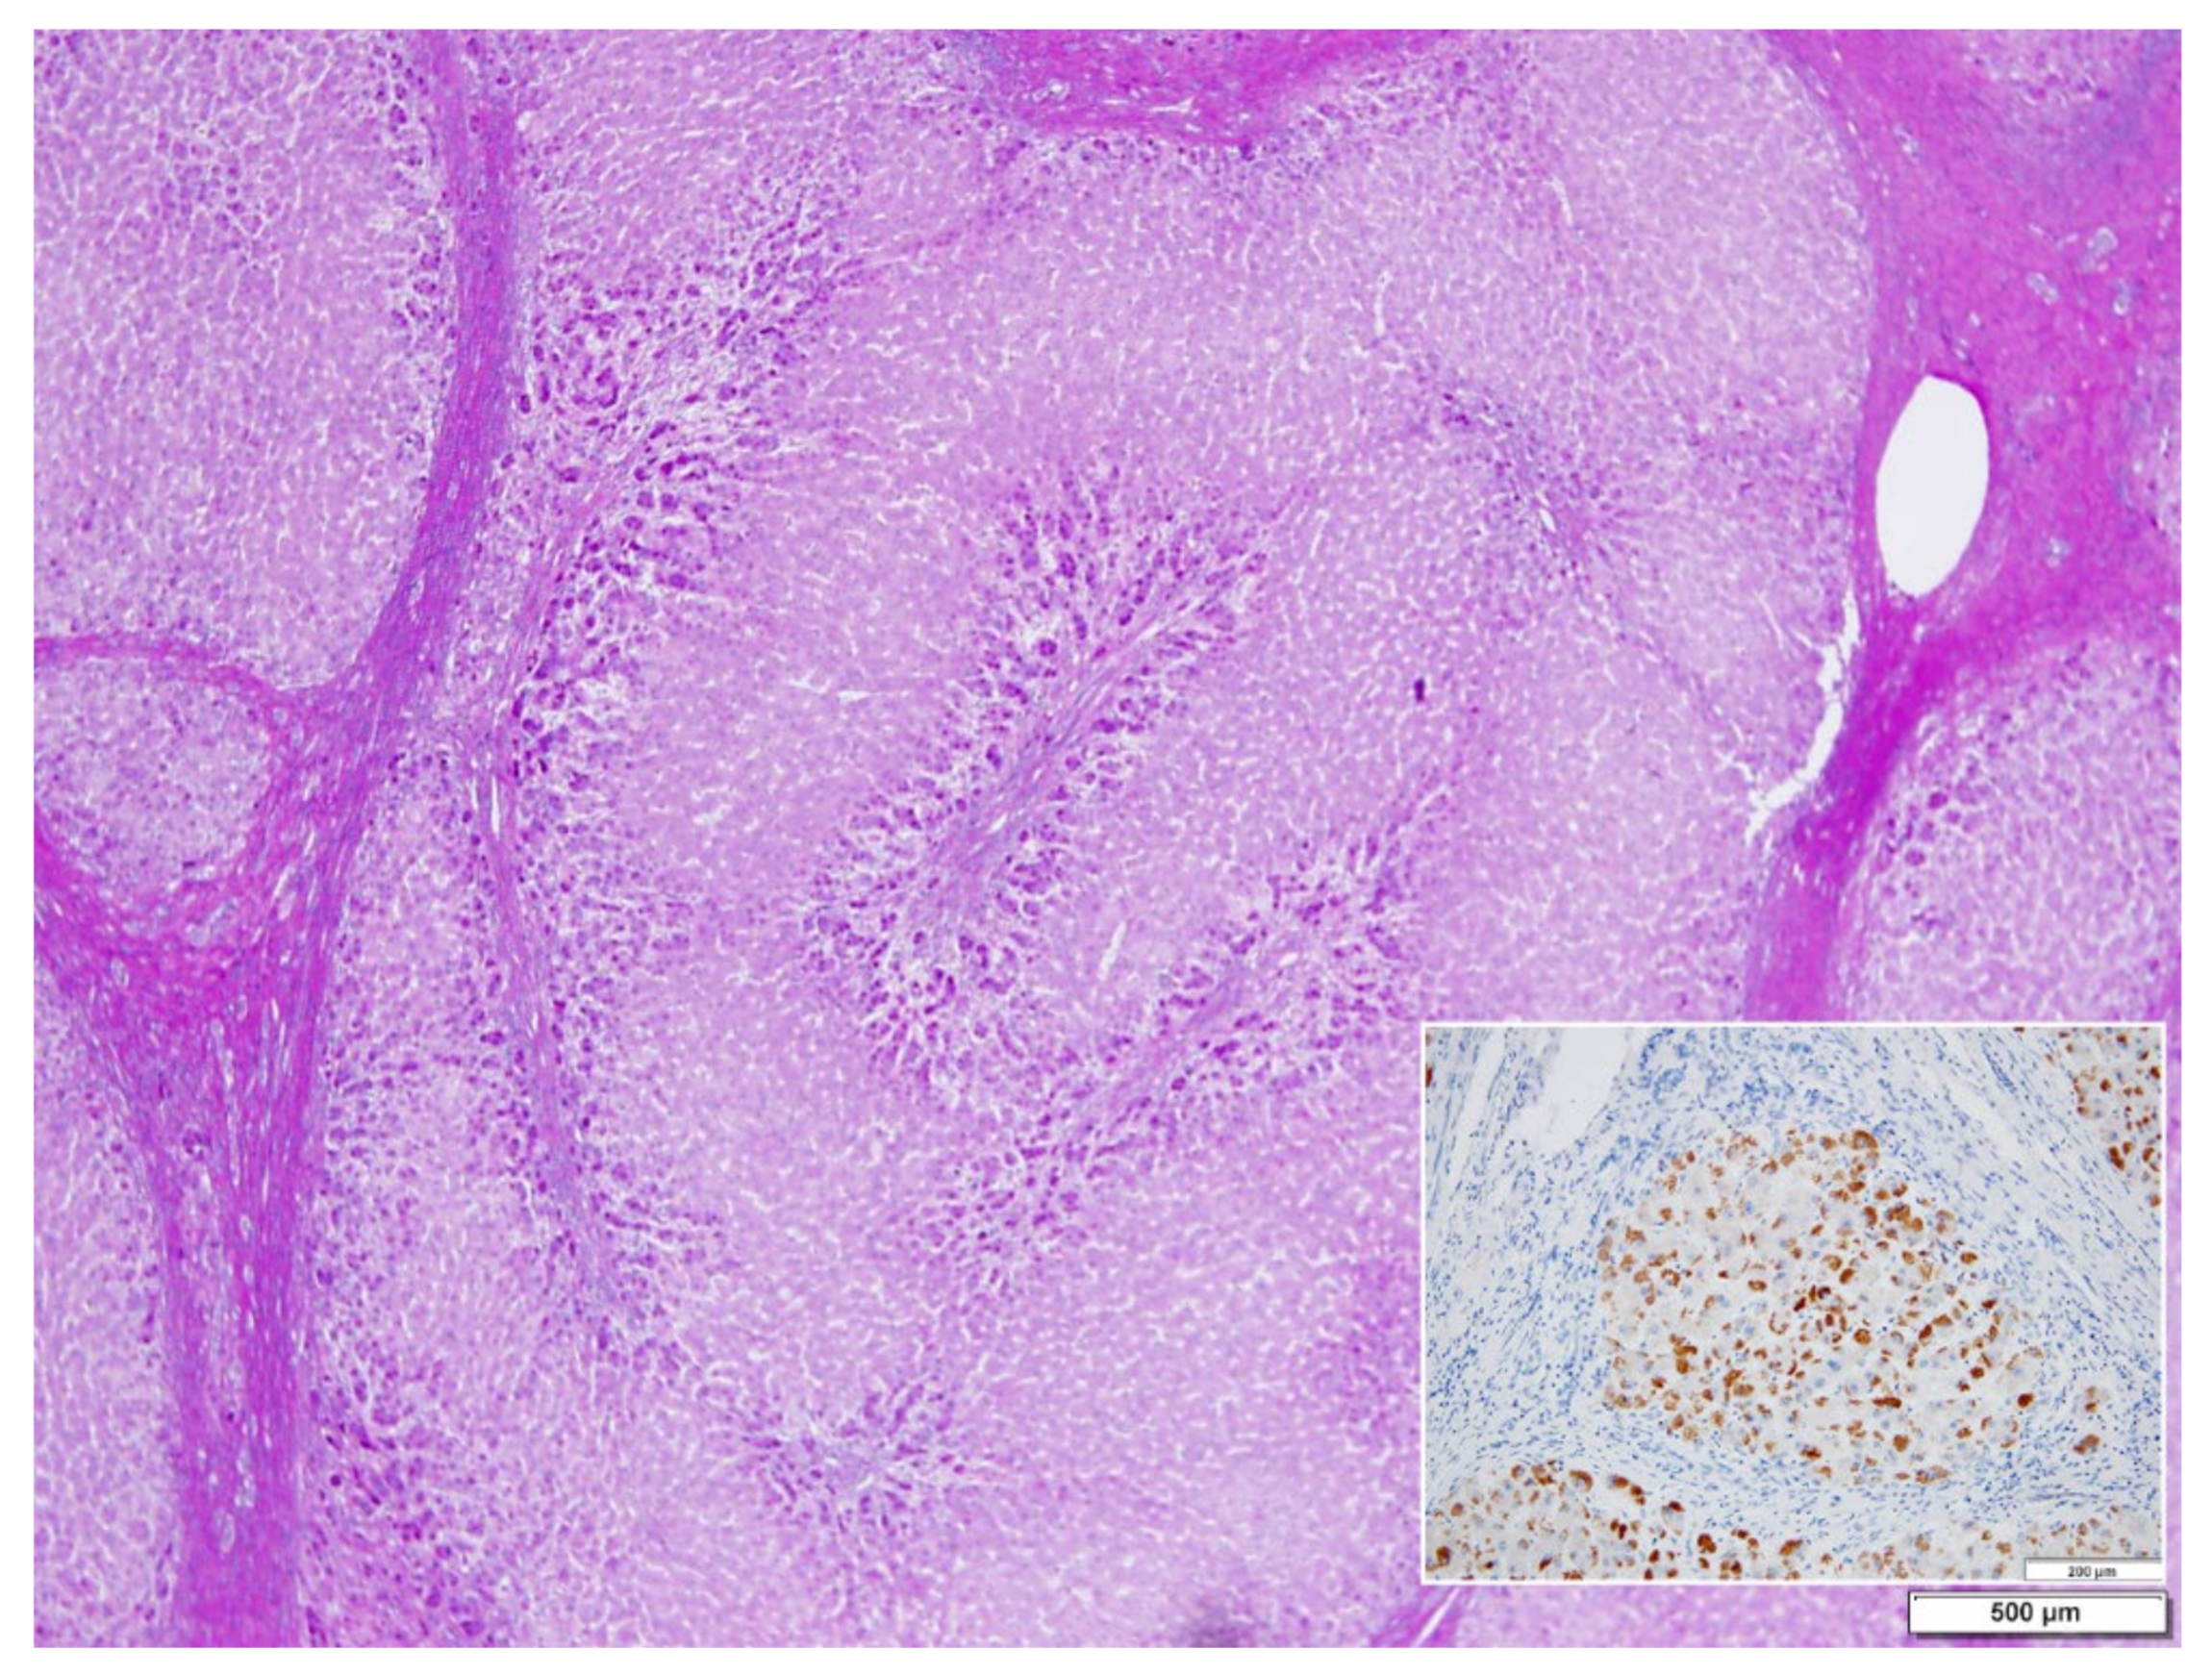

In ZZ patients from groups 2 and 4, the positivity was mainly restricted to zone 1 (periportal) hepatocyte in the form of PAD positive globules (Figure 5) filling up the entire cytoplasm (type I positivity), or unevenly distributed in the intralobular hepatocytes with type II positivity (Figure 5 inset).

Figure 5. Pi ZZ explanted liver. A mixed type (uni- and multilobular) cirrhosis. PASD inclusions are present in zone 1 hepatocytes, separated from the connective tissue of the portal tracts by edema. PAD × 1.25. AAT inclusions fill up the entire hepatocytic cytoplasm in a small nodule. A few positive cells are scattered in the central part (Inset. AAT polyclonal immunostaining × 60).